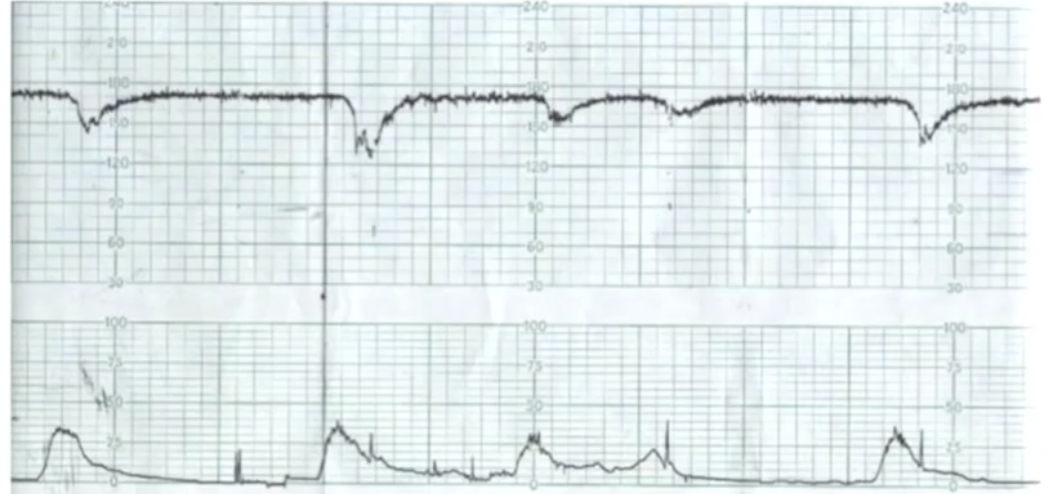

Qual categoria do CTB?

A

Categoria I

Q

Qual a categoria do CTB?

Categoria III